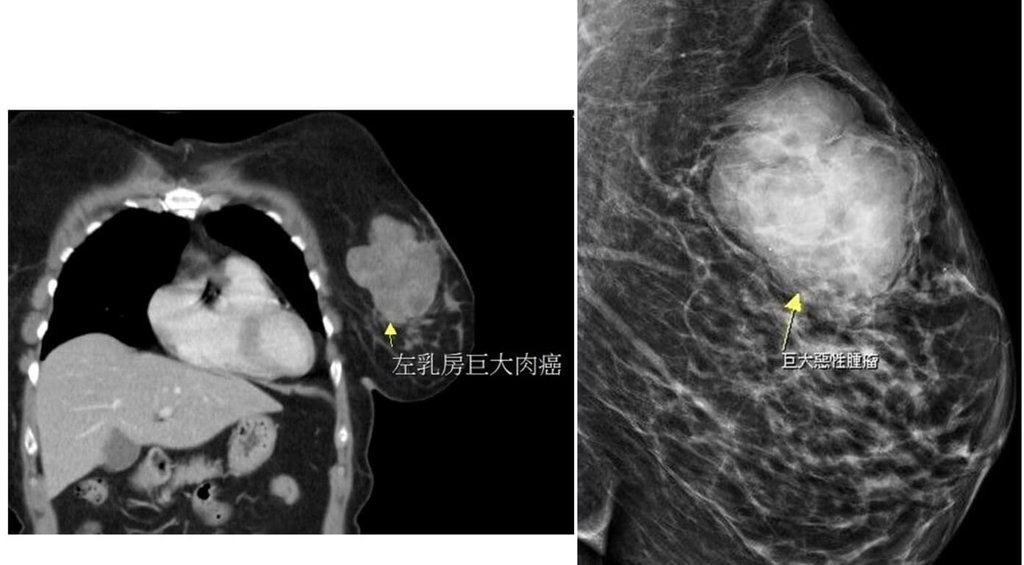

乳房硬塊查出10公分大腫瘤 竟是罕見肉癌

(中央社記者管瑞平苗栗縣29日電)苗栗有婦人單側乳房出現硬塊,就醫檢查出近10公分腫瘤,手術切除病理報告非臨床常見的乳腺癌,而是發生率低且罕見出現在乳房部位的肉癌,醫師提醒身體有異狀務必儘早就醫。

這名56歲黃姓婦人數月來感到左側乳房摸起來有異狀,起初不以為意,直到近日明顯摸到硬塊而且會疼痛才就醫,經超音波檢查已是將近10公分大的腫瘤,大幅增加治療困難度,所幸術後恢復良好,病理報告也證實腫瘤已切除乾淨,持續密集追蹤狀況。